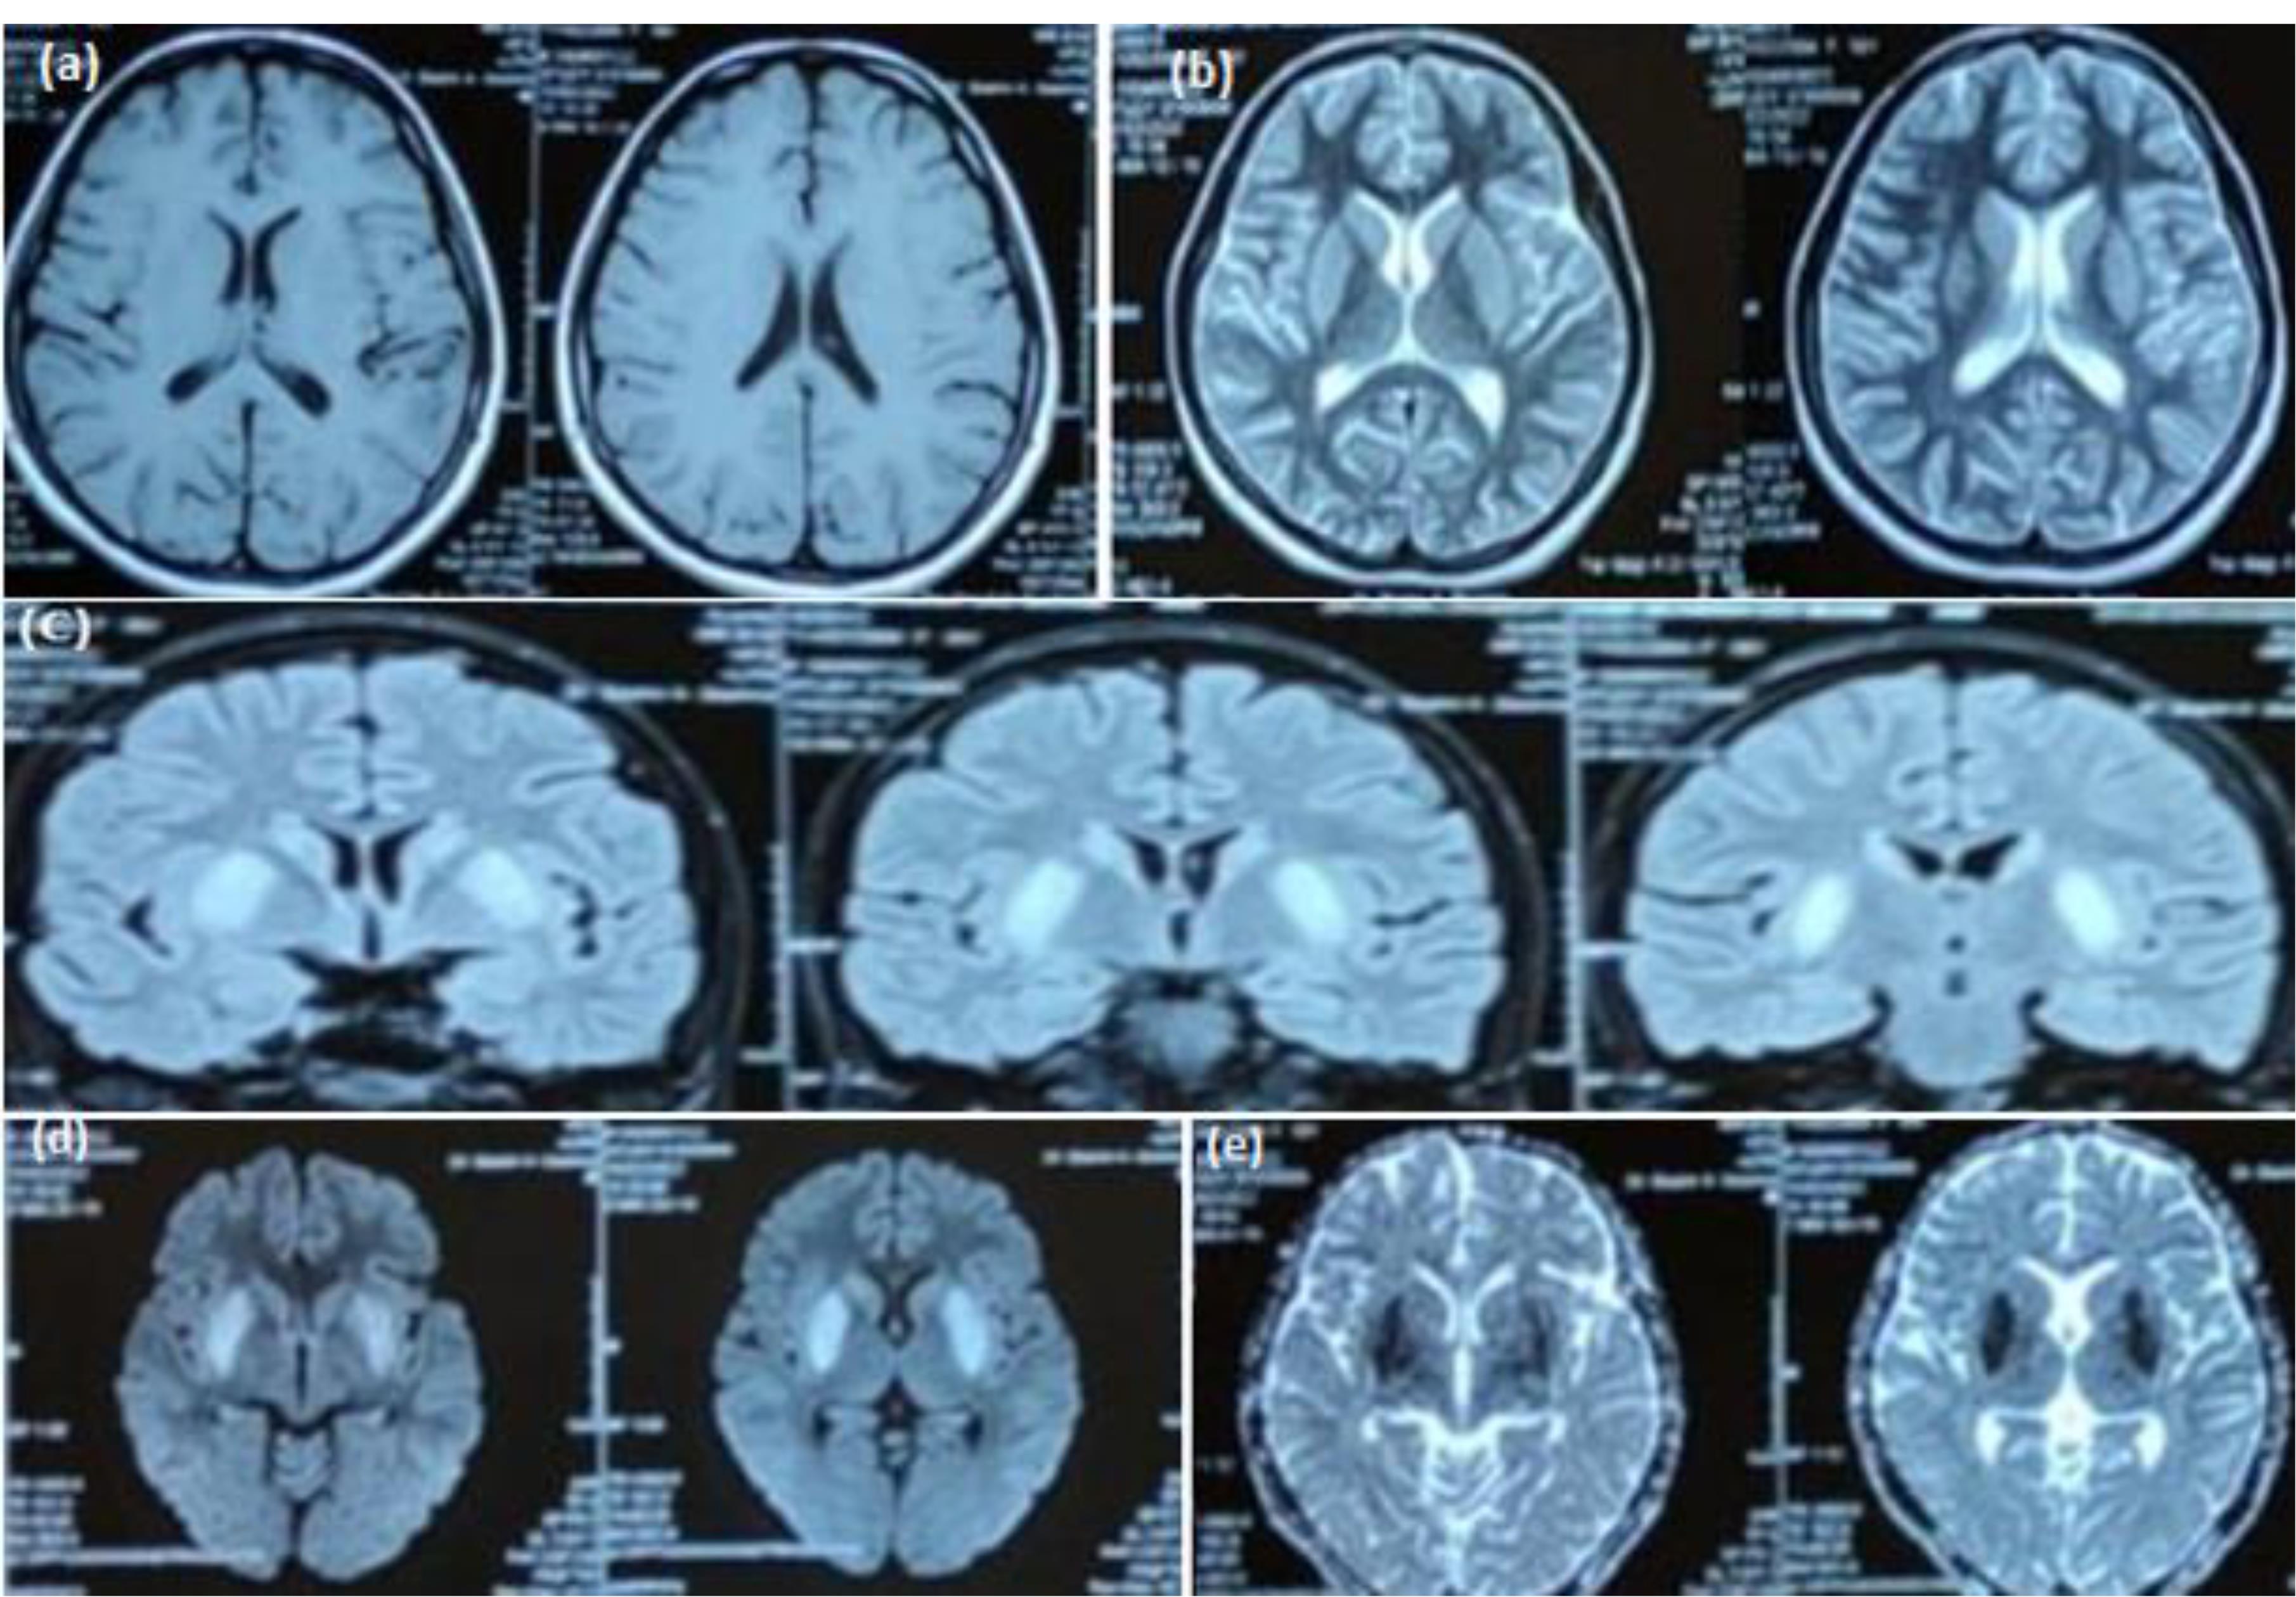

An 18-year-old female with no known comorbidities presented with fever for 15 days, drowsiness for 11 days and generalized tonic clonic seizures (GTCS) for 5 days. Initially, she was managed under the assumption of malaria, but her condition did not improve. She was later taken to another hospital when she experienced her first episode of GTCS, characterized by left-sided gaze, eye up rolling, and subsequent stiffening and jerking of all four limbs. This episode was followed by 15‒20 minutes of post-ictal amnesia. Thirty minutes later, she had another episode in the hospital, and intravenous (IV) administration of Levetiracetam 1 gm was initiated. MRI of the brain revealed bilateral basal ganglia hyperintensities (Figure 1).

Figure 1.

(a) T1 axial view showing hypo-intense signals in bilateral basal ganglia, T2 axial view (b) and FLAIR coronal view (c) showing hyper-intense signals in bilateral basal ganglia, DWI (d) showing diffusion restriction in the region of basal ganglia along with a signal drop out on ADC image (e)

The diagnosis of EBV encephalitis is typically made by detecting EBV antibodies or PCR in the blood or CSF. Detailed CSF reports of these patients show a viral picture. Head CT may be normal in the initial stages. Brain magnetic resonance imaging (MRI) findings may be non-specific and include the involvement of the cerebral hemisphere, basal ganglia, thalamus, brain stem, limbic system, cerebellum, and corpus callosum. In 40% of the patients, MRI may be normal.14 Diffusion restriction may also be seen in a few cases. Brain MRI in our patient showed involvement of the basal ganglia along with diffusion restriction.